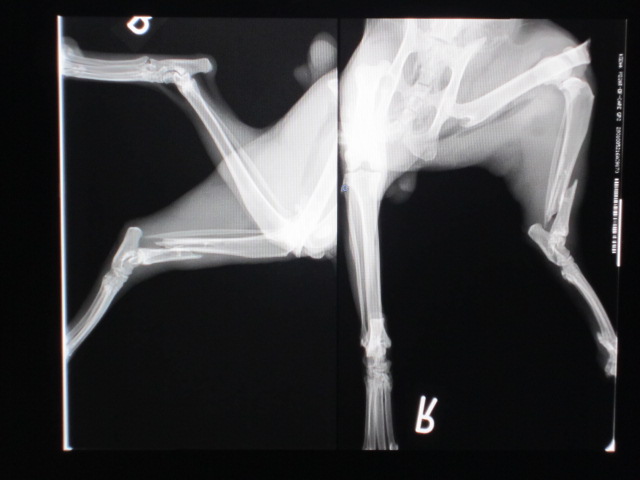

術前のレントゲンです。

右股関節脱臼、左大腿骨遠位端骨折、脛骨遠位端骨折。

骨折はどちらも開放骨折でした。